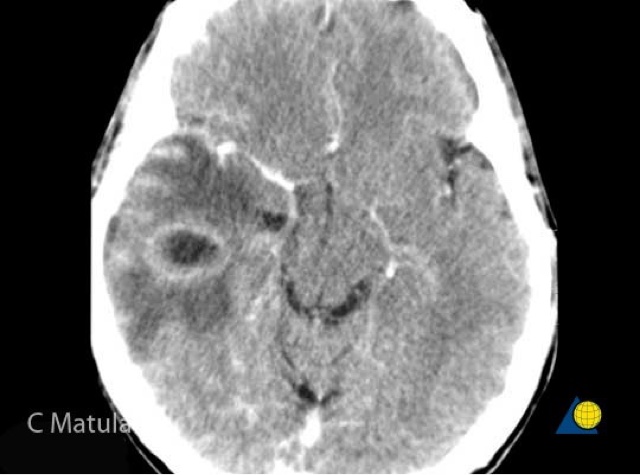

، هو التهاب حاد للأغشية الدماغية المغلفة للدماغ والنخاع الشوكي، المعروفة باسم السحايا. تتعدّد أسباب الالتهاب وتشمل العدوى عن طريق الفيروسات، أو البكتيريا، أو غيرها من الكائنات الدقيقة، وأقل شيوعًا عن طريق بعض الأدوية.

قد يكون التهاب السحايا مهدّدًا للحياة بسبب قربه من الدماغ والنخاع الشوكي؛ من هنا، يُصنّف التهاب السحايا كحالة طبية طارئة.

قد يؤدي التهاب السحايا إلى عواقب وخيمة طويلة الأمد مثل الصمم، والصرع، واستسقاء الرأس ونقيصة معرفية، خاصةً إن لم يتم علاجه بسرعة.

, It is an acute inflammation of the brain membranes coated the brain and spinal cord, known as meningitis. There are several reasons, including inflammation and infection by viruses or bacteria, or other microorganisms, and less commonly by certain drugs.

Meningitis may be life-threatening because of its proximity to the brain and spinal cord; from here, is classified as a case of meningitis medical emergency.

Meningitis can lead to long-term consequences such as deafness, epilepsy, hydrocephalus and cognitive defect, especially if not treated quickly.